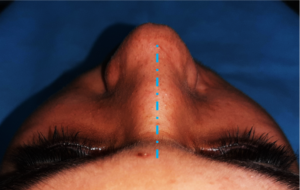

- Fraturas do nariz;

O diagnóstico é feito pelo exame físico dos ferimentos e, nos casos de suspeita de fratura, deve se associar radiografias e tomografias computadorizadas. Esse avaliação poderá ser feita no hospital (se o paciente estiver internado) ou no consultório odontológico. O primeiro passo no tratamento é garantir a vida do paciente. O profissional deve garantir que o paciente esteja respirando bem e sem lesões graves que podem levar a morte rapidamente (como hemorragias severas, obstrução de vias aéreas e lesões de órgãos vitais)